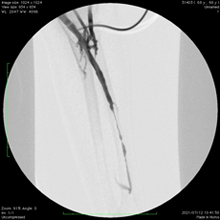

実際の症例①

自己血管シャント狭窄を繰り返し3ヶ月ごとに標準のバルーン拡張術(PTA)を行っていましたが、薬剤コーティングバルーンを併用することで6ヶ月も再狭窄なく透析が可能でした。

3ヶ月ごとに

狭窄繰り返し

バルーン

にて拡張後

再狭窄見られず